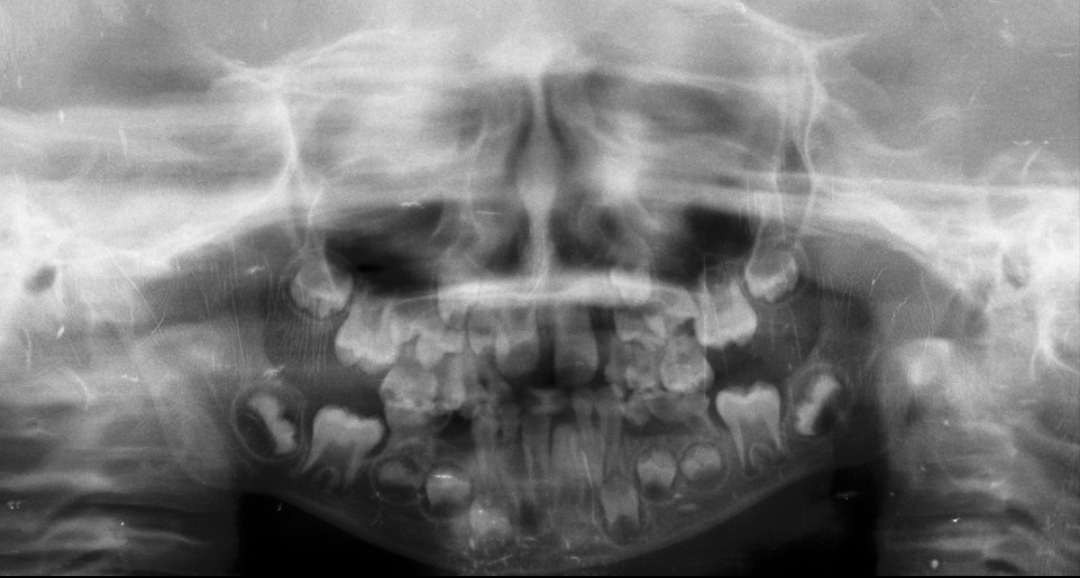

Luego de evaluarla me dice que lo recomendable es hacer un ojal quirúrgico por donde va a salir el diente para que esté pueda terminar de bajar, entre una cosa y otra no había podido llevarlo, hasta que hable con la hija de una amiga que estudia odontología y está trabajando con una doctora y ella lo vería a las 8:30 am, a esa hora estábamos en su consultorio.

Luego de evaluar la placa empieza la película de terror, Eliezer es demasiado nervioso y aunque le explicamos que pasaría,no es lo mismo estar en el momento, la doctora muy amable lo evaluó y dijo definitivamente hay que cortar eso es una cirugia menor pero cirugia al fin.